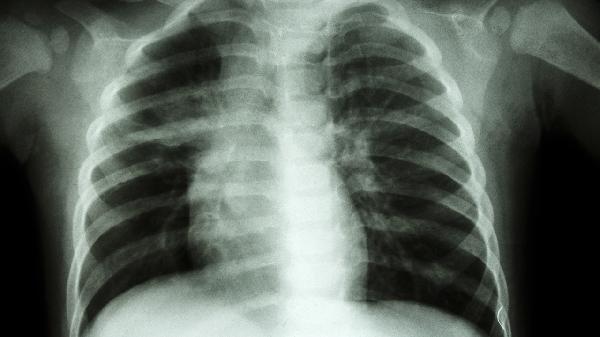

肺部感染引发的胸痛常伴随咳嗽发热,听诊可闻及湿啰音。头孢克肟分散片或左氧氟沙星片适用于细菌性肺炎,配合氨溴索口服液促进排痰。需完善血常规和胸部CT检查,重症患者可能需住院静脉用抗生素治疗。